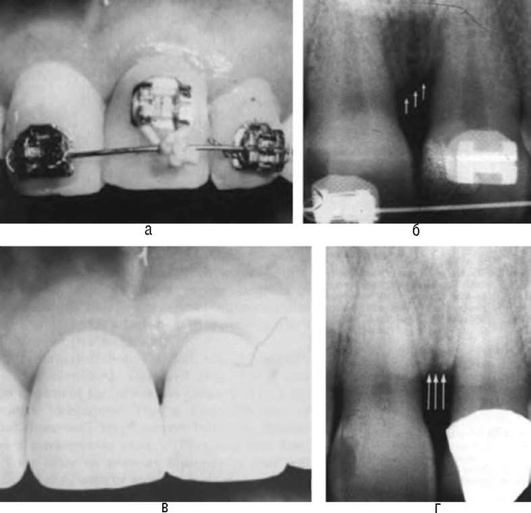

На рентгенограмме нижней челюсти в боковой проекции обращают внимание на положение нижнего зуба мудрости, состояние его периодонта и окружающей кости, отношение его к ветви и каналу нижней челюсти (рис. 14-17).

image

Рис. 14-17. Рентгенологическая картина ретенции зуба мудрости